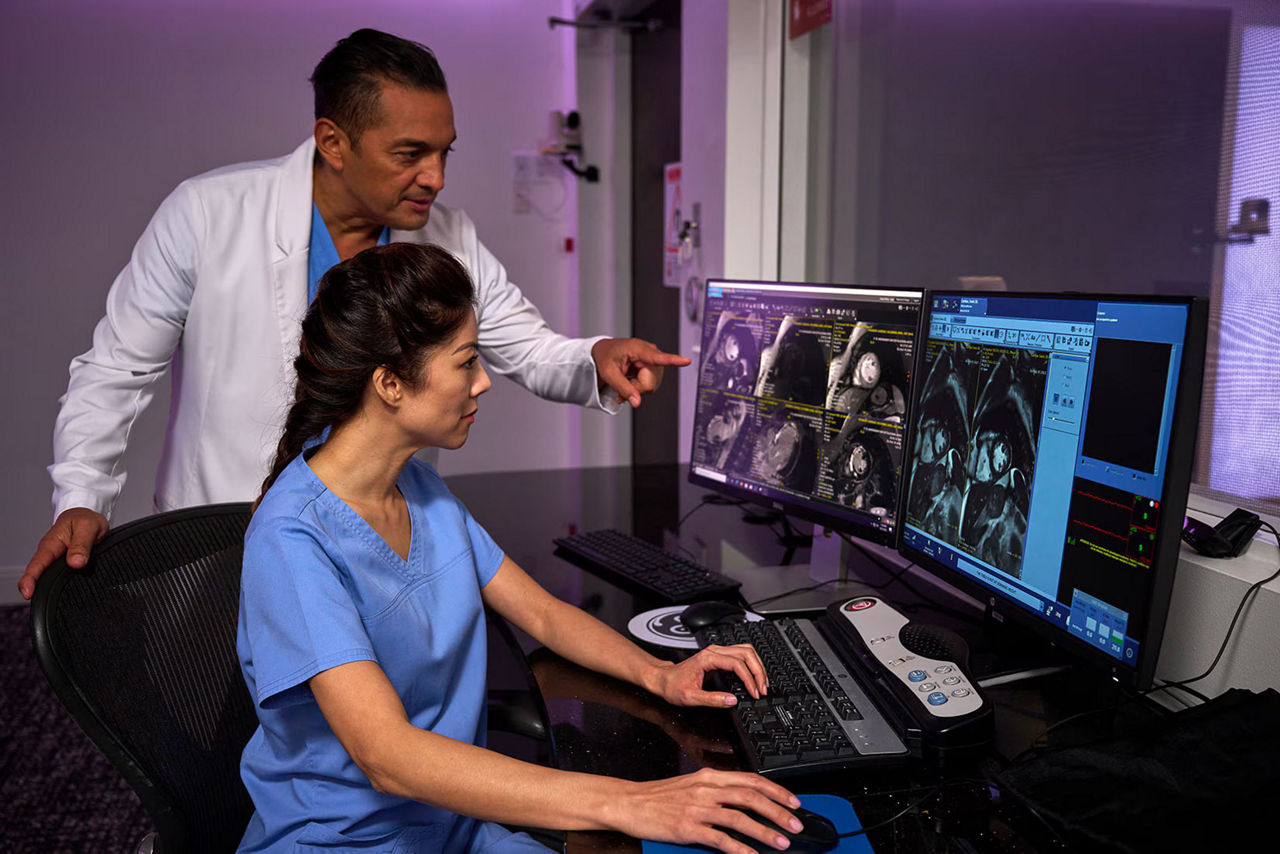

AI-Enhanced cardiac MR

Perform quantification and mapping with revolutionary deep learning